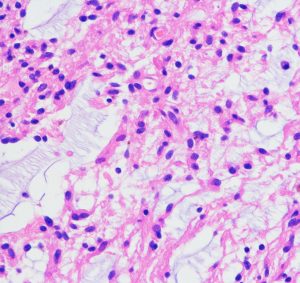

病理所見では,幼児型のpilomyxoid astrocytomaの部分が混在します。その部分が増殖と腫瘍増大に関わっています。T2強調画像で高信号でガドリニウム増強される部分です。

myxoidな部分です。右下のMIB-1染色では3%ほどの陽性率であり,数年単位では腫瘍増大があり得ることを示します。柔らかく出血性で吸引摘出できる部分の腫瘍です。IDH wild type, BRAFV600 wild type, H3K27 wild type, FGFR1 N546K mutationでした。

厚く肥厚した視神経鞘の内部の視神経組織はほとんど腫瘍に置き換わっていて,GFAPで染色され高度の石灰化を伴います。これは腫瘍というよりも瘢痕化してしまった,adult-type pilocytic astrocytomaに認められる所見です。

Rosenthal fiber, eosinophyric granular body, psammoma bodyなどが認められ,成熟しきって退行変性に移行するpilocytic astrocytomaの像です。この部分は増大しません。線維性に極めて硬い組織です。